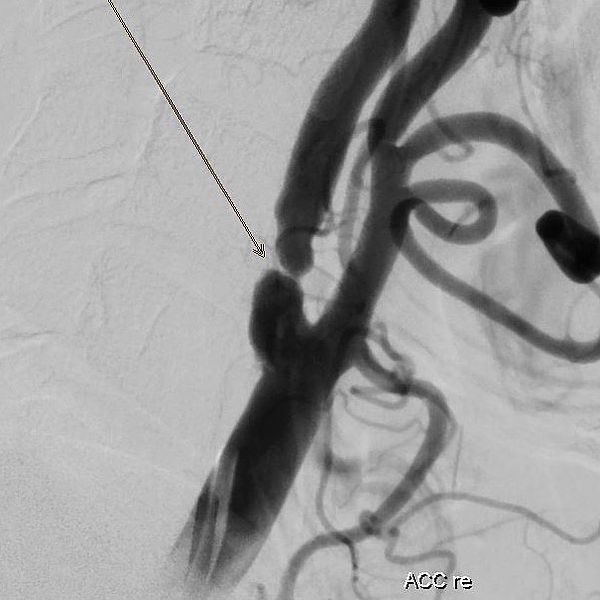

Die interventionelle Therapie von Stenosen erfolgt über einen Gefäßkatheter, der meist von der Leiste oder vom Arm bis in den Halsbereich vorgeschoben wird. Dort kann mit Hilfe eines Ballons die Engstelle zunächst aufgedehnt und dann mit einer Gefäßstütze (Stent) stabilisiert werden.